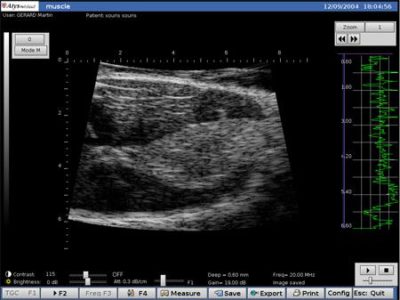

Ratón Músculo